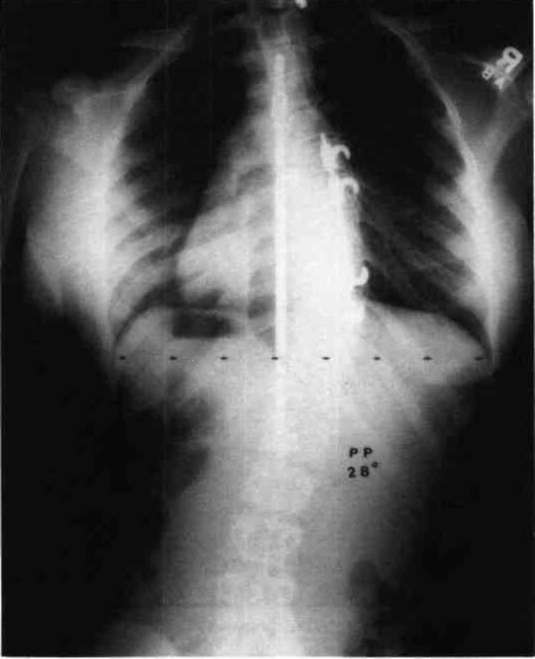

From www.researchgate.net

xray, showing location of the Harrington rods. Download Scientific Harrington Rod Material Historically, this rod was implanted along the. The harrington rod (or harrington implant) is a stainless steel surgical device. Since the introduction of the harrington rod in 1962, new rod materials and concepts have been developed. It's attached to the spine with the goal of holding it in a straighter position so its vertebrae can't become more. The straight rod,. Harrington Rod Material.